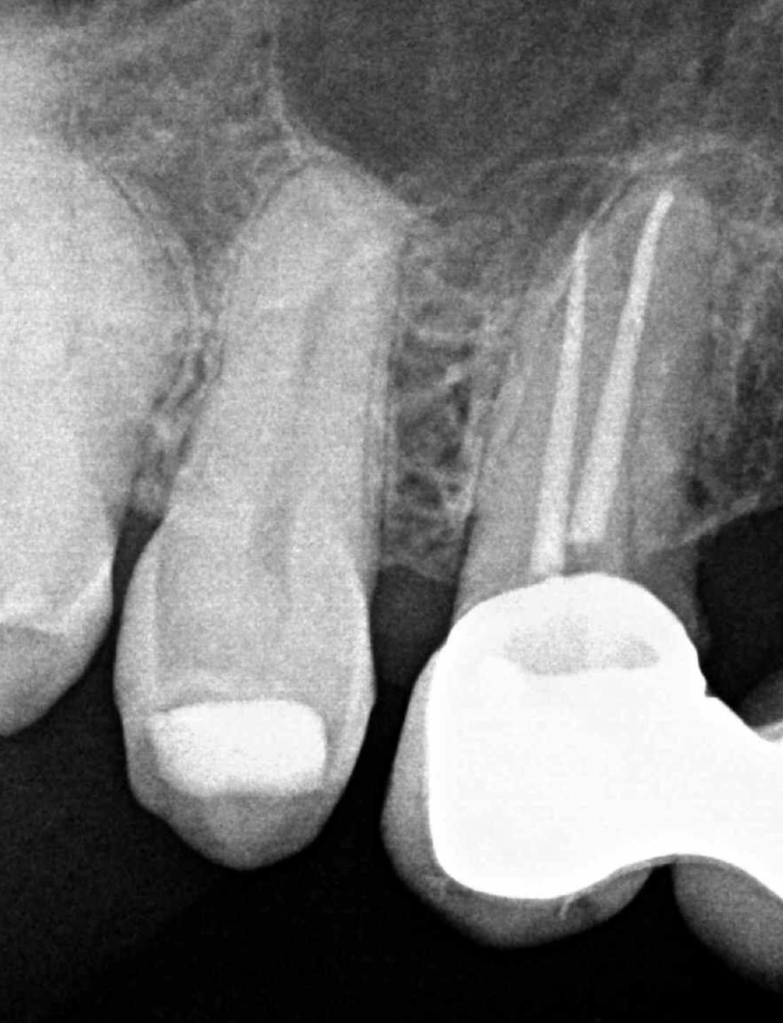

Reco pared vesticular